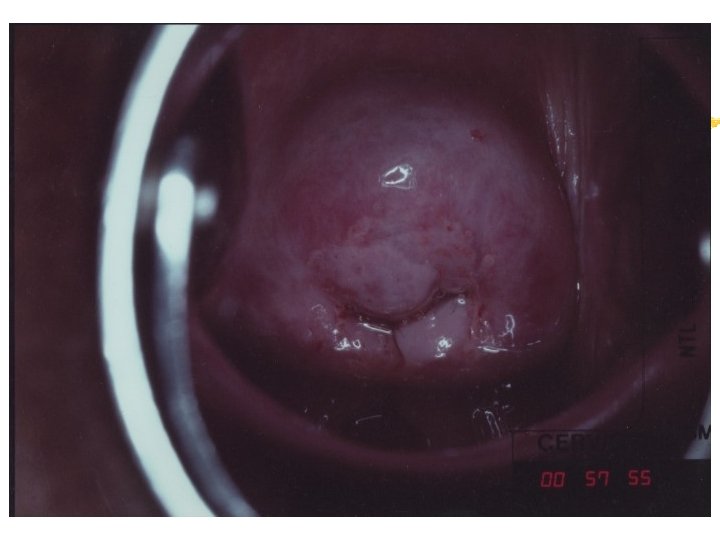

Cervicography: This is NOT Colposcopy High-quality colposcopic-type photography of the cervix Cervicoscope - Hand-held camera with a macrolens and a ring-flash Cervicogram - 35 -mm photo slide is taken Principles Recognition of lesions by means suitable magnification and illumination Fix up the problems of colposcopy 1. a less expensive form 2. noninvasive method 3. do not require expert skill

Procedures of cervicography A) Taking a 35 -mm cervicogram (1) Insert speculum and open as wide as possible … expose an entire cervix and upper vagina (2) Apply first application of 5% acetic acid by dabbing … cleanse the cervix of blood and mucus (3) View the cervix through the cervicoscope … allows time to begin taking epithelial change (4) Apply second application of acetic acid. (5) Take two cervicogram pictures B) Developing the images C) Interpreting a magnified image that was projected on the screen (1) Negative if no definitive lesions are visible (2) Atypical if there was evidence of acetowhite lesion of doubtful significance (3) Positive if there was evidence of a minor or major-grade lesion or cancer